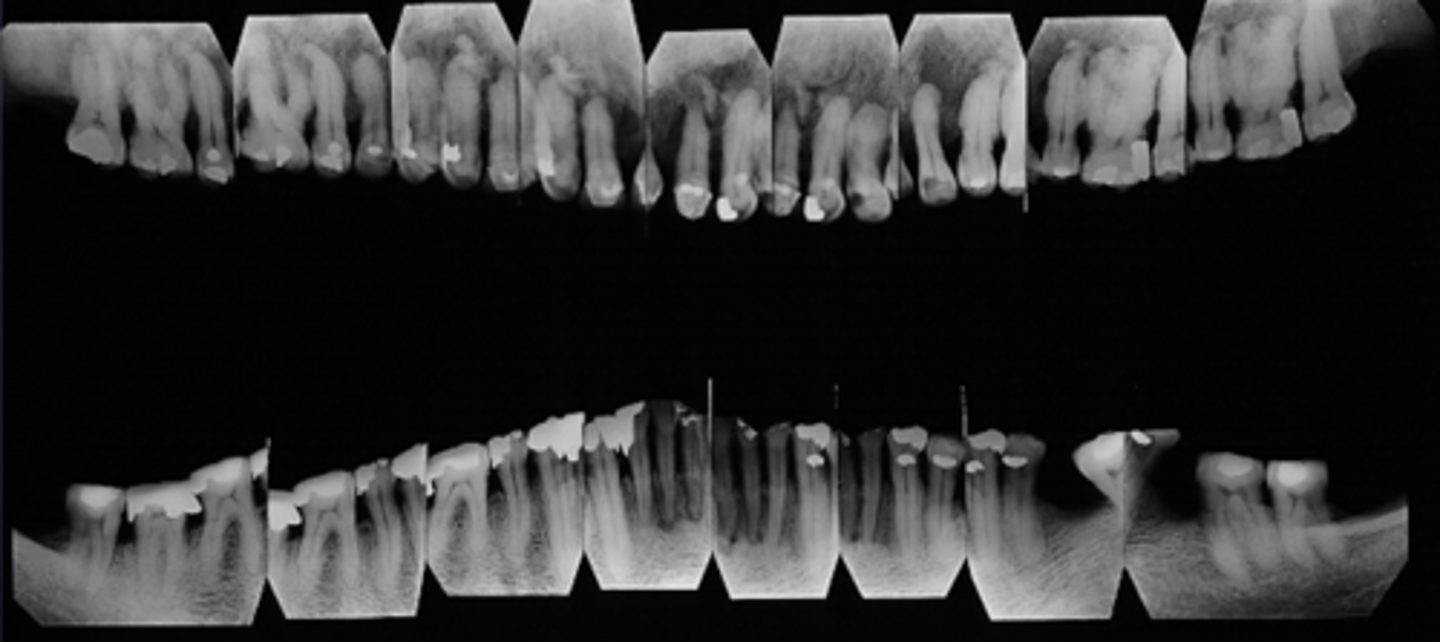

how would you describe this lesion? (not the giant cavity btw)

A. defined, corticated, periapical radiolucency causing loss of lamina dura and PDL space on #6-7

B. defined, non-corticated, periapical radiolucency causing loss of lamina dura and PDL space on #6-7

C. ill-defined, circular radiolucency located above tooth #7

D. well-defined, corticated, radiopacity

- Also note epicenter located above apex # 7 which has large dental caries.

What category would this lesion be part of?

Inflammation/benign

all of the following could be a differential diagnosis for the following lesion EXCEPT?

A. radicular cyst

B. Periapical granuloma

C. apical rarefying osteitis

D. renal osteodystrophy

what category would this lesion be classified into?

inflammatory/benign cystic